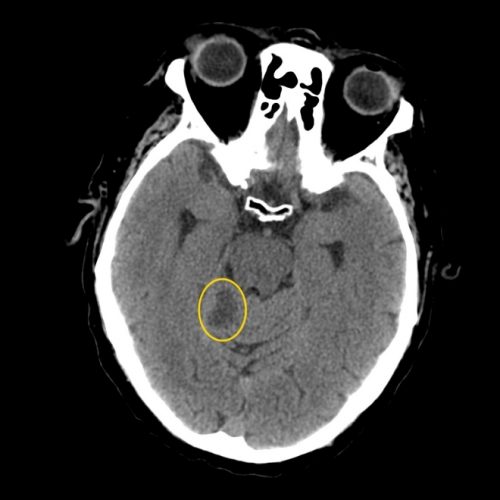

Методы диагностики мозговой кисты

Пациенты редко обращаются к врачу с подозрением на наличие кисты. Так как признаки заболевания очень не специфичные, рядовой человек не может отличить ее от ухудшения зрения, проблем нервной системы, последствия травмы. Поэтому проблема обнаруживается обычно в ходе общих регулярных обследований (диспансеризация или медицинское обследование перед вступлением в некую должность). В ходе диспансеризации кисту может обнаружить терапевт по описанным симптомам либо специалист по рентгену или МРТ, КТ.

Список болезней, симптомы которых схожи с проявлениями кисты головного мозга, огромен. Поэтому при подозрении на наличие камеры с жидкостью сразу назначают серьезное обследование – компьютерную томографию, МРТ или рентген.

Рентгеновское обследование позволяет обнаружить нехарактерные участки серого вещества. Лакуны на снимке будут выглядеть, как контрастные области, резко выделяющиеся на фоне остальных, однородно окрашенных частей мозга. Проблема такого исследования в том, что размер капсулы может не превышать 1-2 мм, поэтому ее очень сложно разглядеть. Если образование небольшое, понадобятся более точные примеры аппаратов – МРТ или КТ.